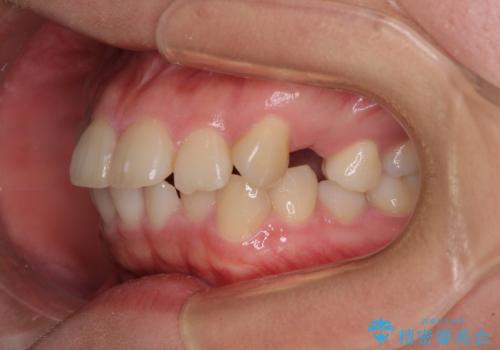

- 口元の閉じにくさを気にして来院された患者様です。

地元で矯正治療を始める予定で上顎左右第1小臼歯2本を抜歯したものの、その後転居したため治療が滞っているとのことでした。

上下ともに歯列が前方に突出していたため、上下左右の第一小臼歯4本を抜去する方針(既に上顎は抜歯されています)で、ワイヤー装置による矯正治療を行うこととしました。

舌の突出癖による影響もあったため、舌のトレーニングを並行して実施しました。